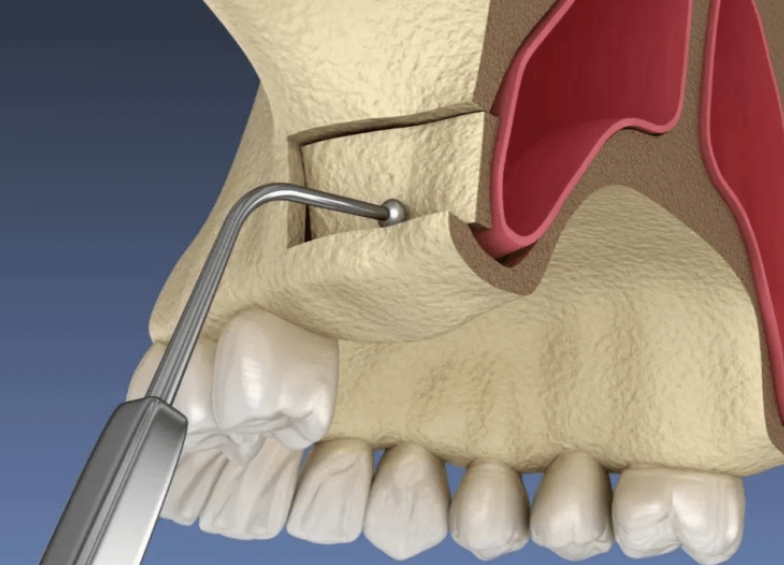

رفع الجيوب الأنفية

تمكين الزراعة في الفك العلوي

إجراء متخصص لرفع أرضية الجيب الأنفي لتوفير ارتفاع عظمي كافٍ في الفك العلوي لنجاح زراعة الأسنان.

الطريقة الجانبية

تقنية تقليدية لتعزيز العظم بشكل كبير

الطريقة من القمة

طريقة طفيفة التوغل لاحتياجات العظم المتوسطة

زراعة متزامنة

رفع الجيب وزراعة الأسنان في آن واحد عند الإمكان